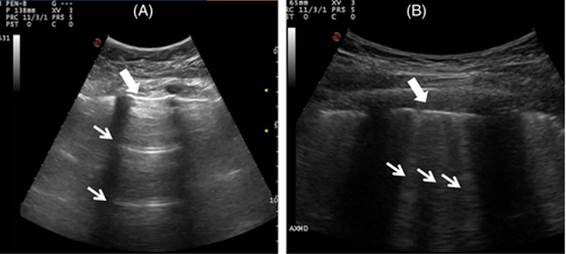

En estecontexto, la ecografía pulmonar ha surgido como una herramienta potencial para la evaluación de EPI en AR, siendo potencialmente útil tanto en el diagnóstico como en el seguimiento.14,15) Es una técnica no invasiva, sin radiación y accesible que tiene capacidad de detección de alteraciones pulmonares.4,14 La prueba se considera positiva ante la presencia de al menos cinco líneas B totales o más de tres líneas B en 2 sitios contiguos, con artefactos múltiples y difusos de distribución bilateral.16)Figura 1.

Figura 1: Ecografía Pulmonar: Características ecográficas de pulmón normal y de enfermedad pulmonar intersticial (EPI). (A): Pulmón normal, líneas A (líneas horizontales regulares). (B) Imagen de un pulmón con afectación pulmonar fibrótica, evidencia de líneas B; a su vez se observa pleura irregular. Tomado de: Otaola M, et al 16